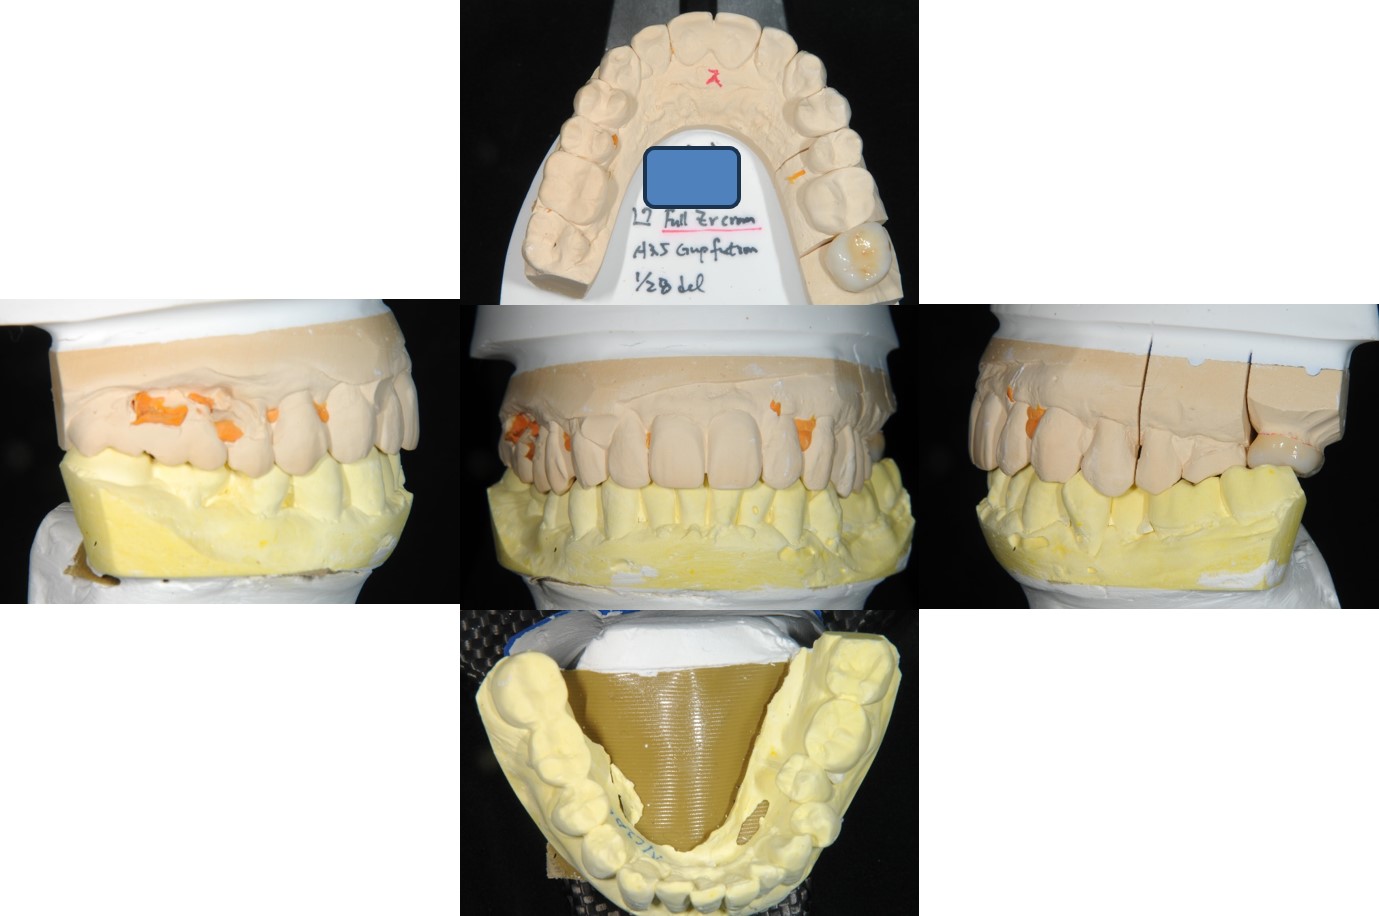

咬合器上製作全瓷冠